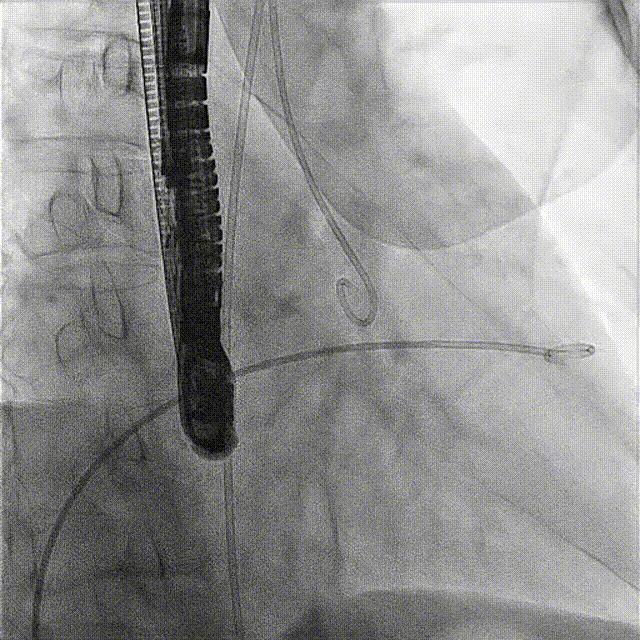

術(shù)前DSA

術(shù)前經(jīng)過全面系統(tǒng)的評估后,考慮患者存在高齡、心功能減低、三尖瓣瓣環(huán)重度擴(kuò)張(三尖瓣極重度反流)等高危因素,因此廈心結(jié)構(gòu)心團(tuán)隊(duì)聯(lián)合超聲心動、麻醉及護(hù)理團(tuán)隊(duì),制定了詳盡的圍術(shù)期治療方案及術(shù)中治療難點(diǎn)預(yù)案。術(shù)中,由王焱院長主刀,在蘇茂龍主任超聲心動團(tuán)隊(duì)的輔助,上海市第一人民醫(yī)院陸方林主任的協(xié)助下,僅用時30分鐘,即順利完成了三尖瓣原位置換的手術(shù)。術(shù)中患者血流動力學(xué)穩(wěn)定,術(shù)后即刻顯示LuX-Valve Plus瓣膜位置良好,固定穩(wěn)定,瓣膜功能正常,無瓣周漏。